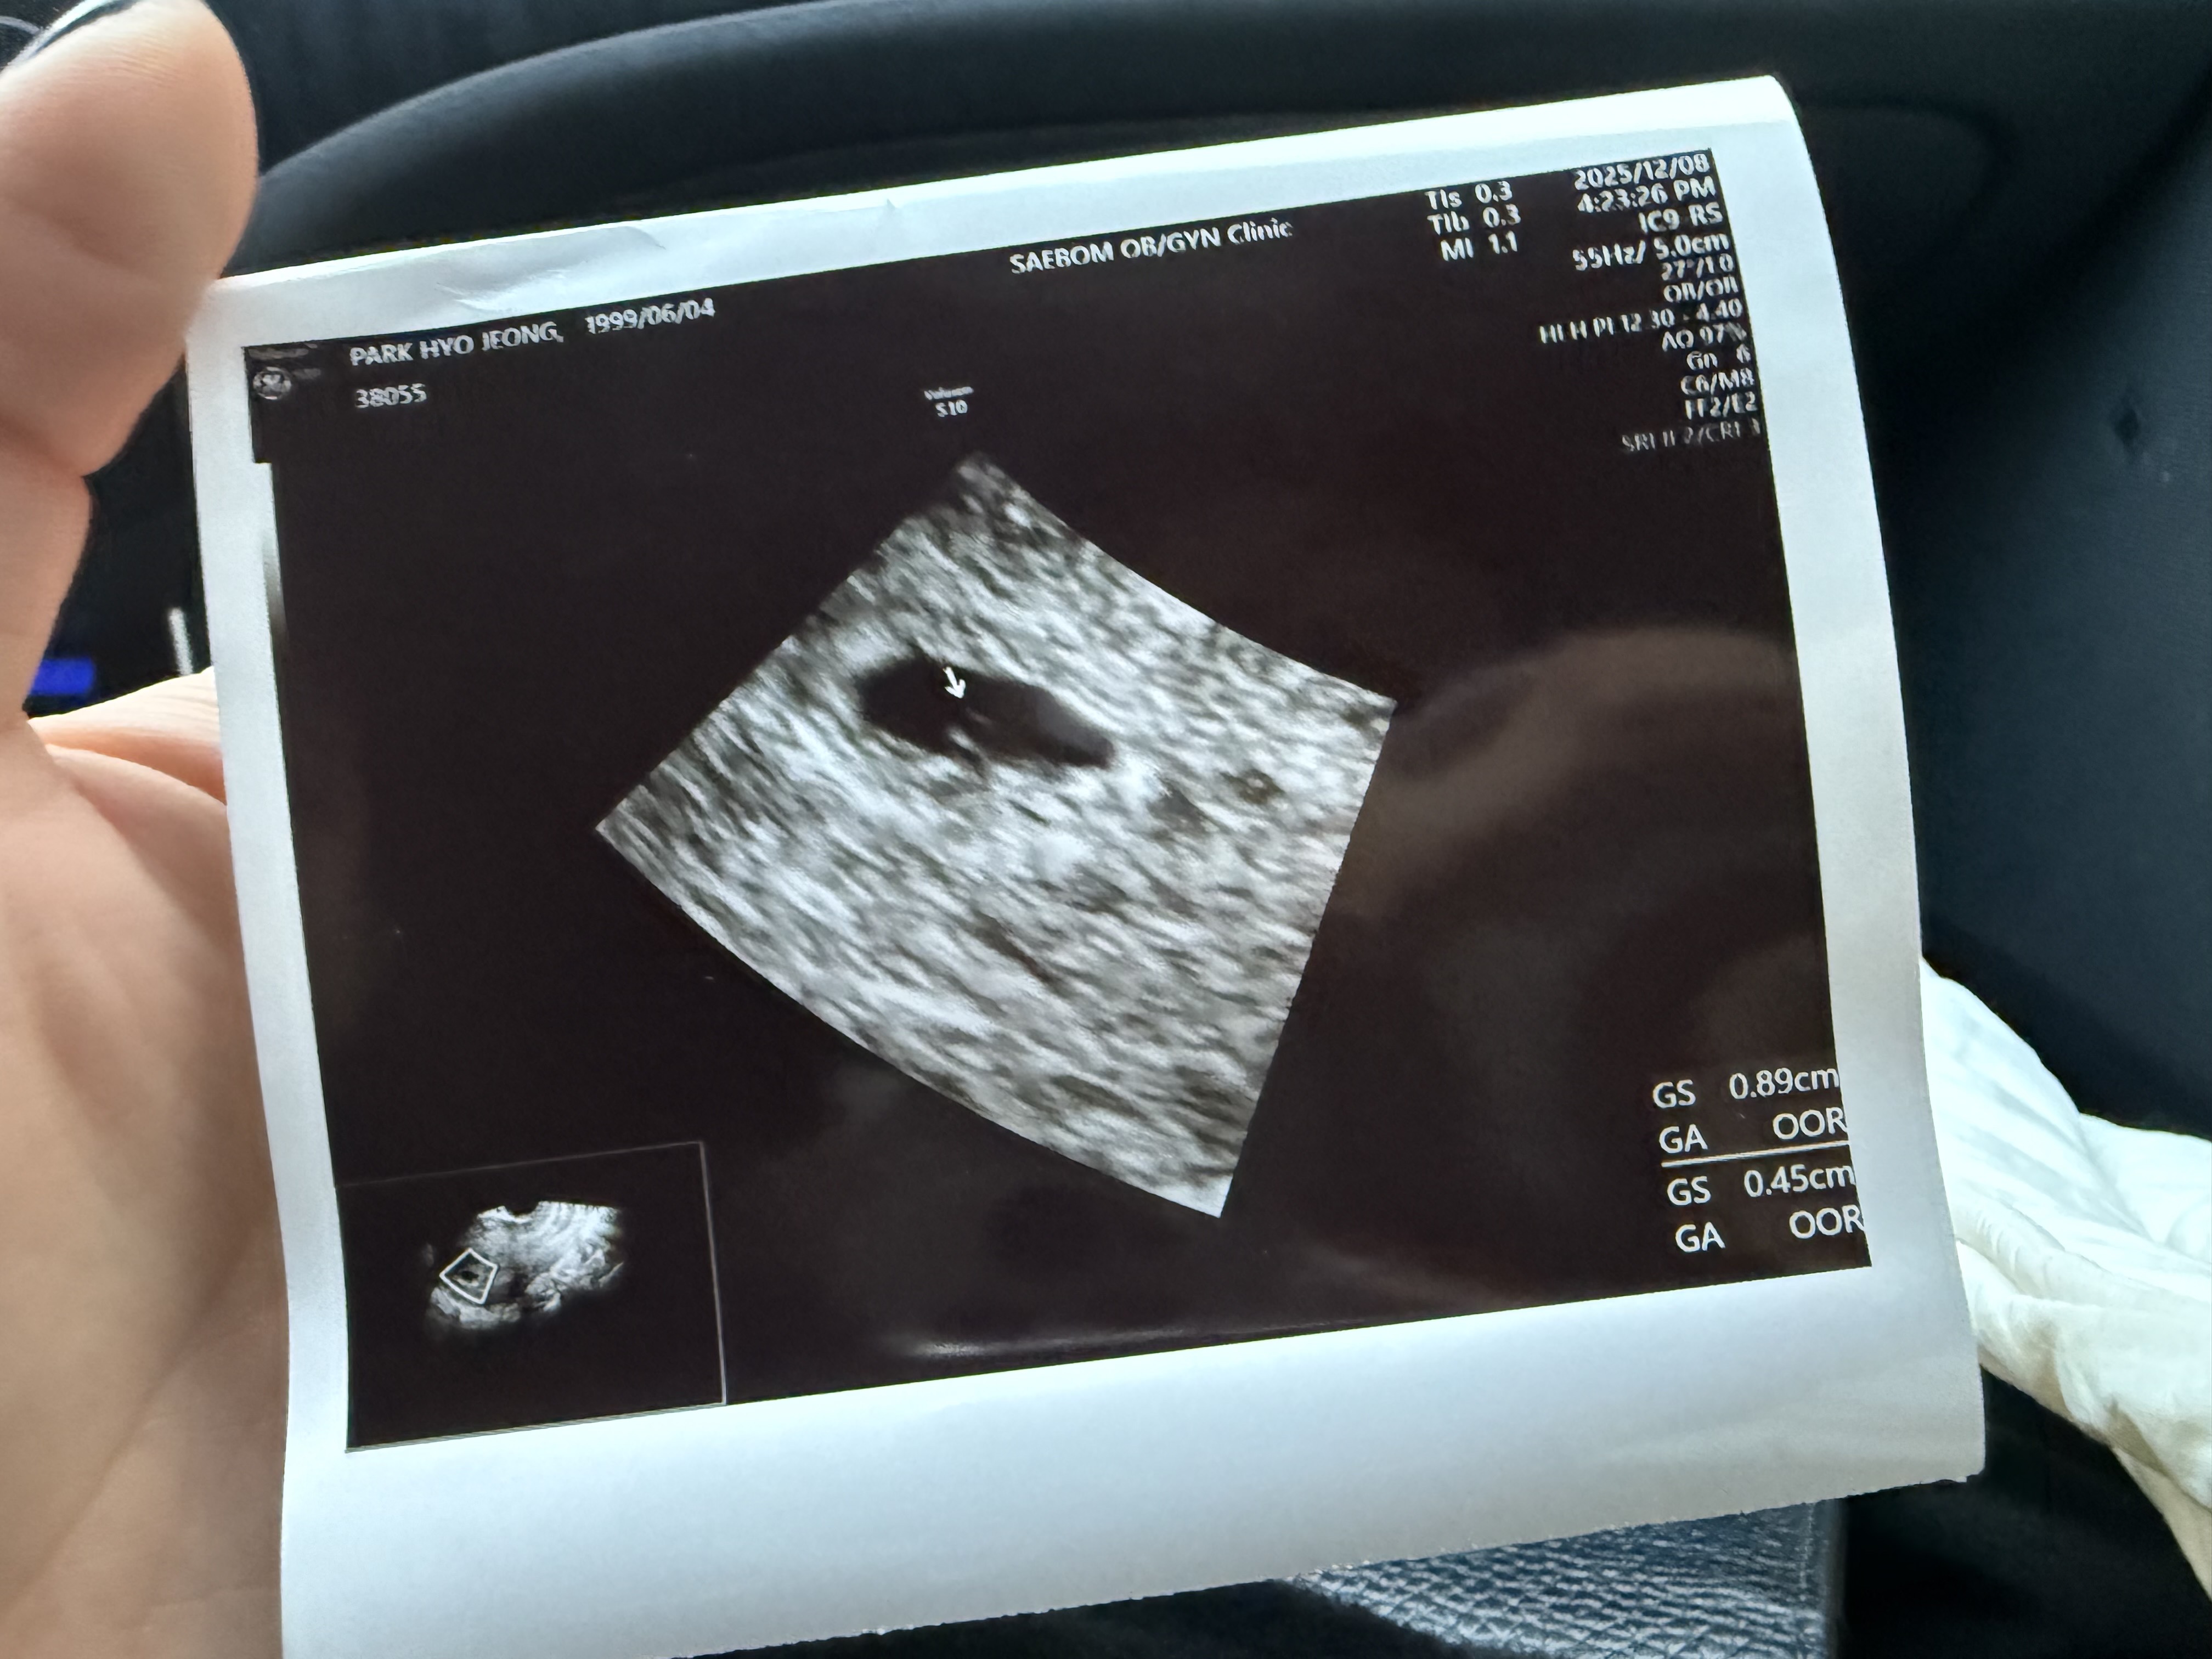

착상혈로인한 병원 그리고 커진 아기집난황❤️

오늘 4주6일찬데 혈이있어서 병원가니 착상혈이라고 하면서 더커진 아기집이랑 난황까지 봤어요!!! 🥺💓 예비말띠맘님들 인스타 소통해요 아이디 주시면 팔로우갈게요 ✨❤️